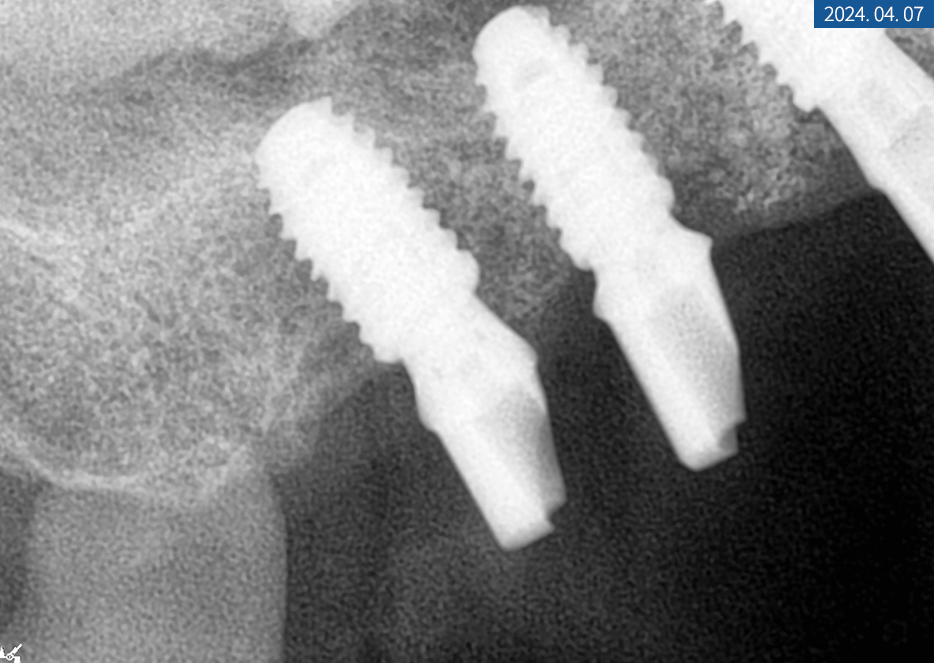

그리고 환자분의

우측 임플란트 수술을 진행했습니다.

이 부위는 모두 2차 수술까지 필요한 경우로,

임플란트 픽스처 고정 후

커버스크류를 씌우고 잇몸을 봉합한 뒤

다음 내원 때 뵙기로 했습니다.

4개월의 골 유착 기간을 갖고

내원해 주신 환자분의

#14번 치아는 본을 뜨고 보철물 수복을 해드렸으며

2차 수술을 진행한 #16, #17, #46, #47번은

잇몸을 열고 커버 스크류 제거 후

힐링 어버트먼트를 체결해 드렸답니다.